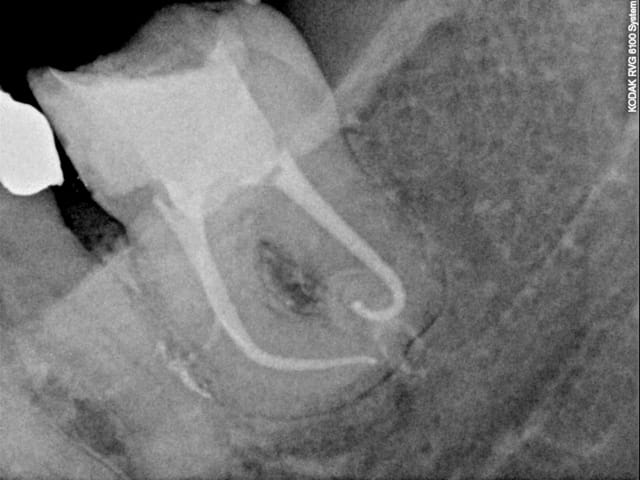

Canal MV au milieu c'est quoi cette connerie?

pas vu, peut etre un bout de thermocompacteur mais il me semble un peu petit sinon superposition des deux canaux? demain je te mats l'autre radio avec une autre incidence je regarderai, mais toute façon pas grave du tout (sauf pour mon instrument)